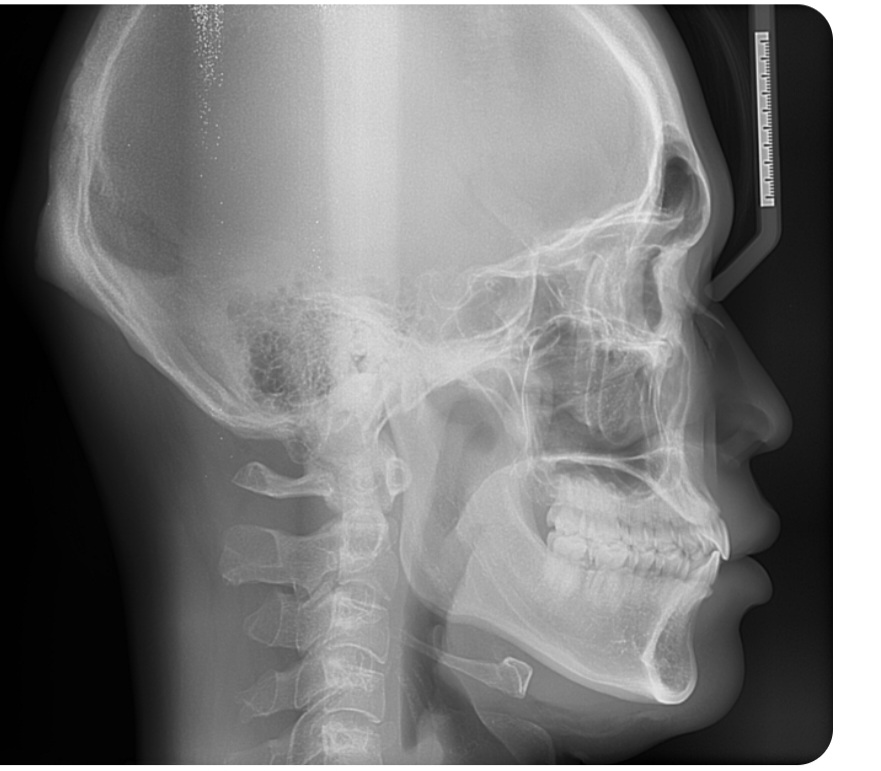

돌출입과 부정교합으로 인해

입이 벌어지게 되면 구호흡을하는 경우도 있습니다.